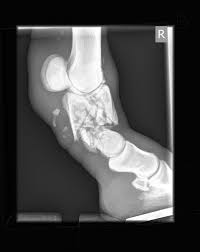

A horrible pastern fracture

The pastern can occasionally be a spot where some rather catastrophic fractures can occur. Most of these fractures occur when an extreme amount of stress gets put on the leg. The pastern, which is both 1) near the ground, where the forces concentrate, and 2) not that big of a joint, honestly, takes a whole lot of stress.

Fractured pasterns especially show up when a horse has to turn quickly. The leg can get stuck in the ground and when it twists, the pastern can shatter. If for no other reason, that’s why you need to be very careful when turning your horse out to run after he’s been cooped up in a stall. You can read about why you should be careful turning out your horse is you CLICK HERE

The good news – such as it is – is that a good number of horses with fractured pasterns can be returned to soundness by surgery (you don’t always have to put a horse with a broken leg to sleep). The prognosis for recovery depends on the fracture and whether the fracture occurs in a front or back leg (the prognosis is better in the back leg, since a back leg has to carry less weight), and surgery is expensive, but repair can be done (I take care of one horse in my practice who’s doing great as a trail horse after a right hind pastern fracture years ago).